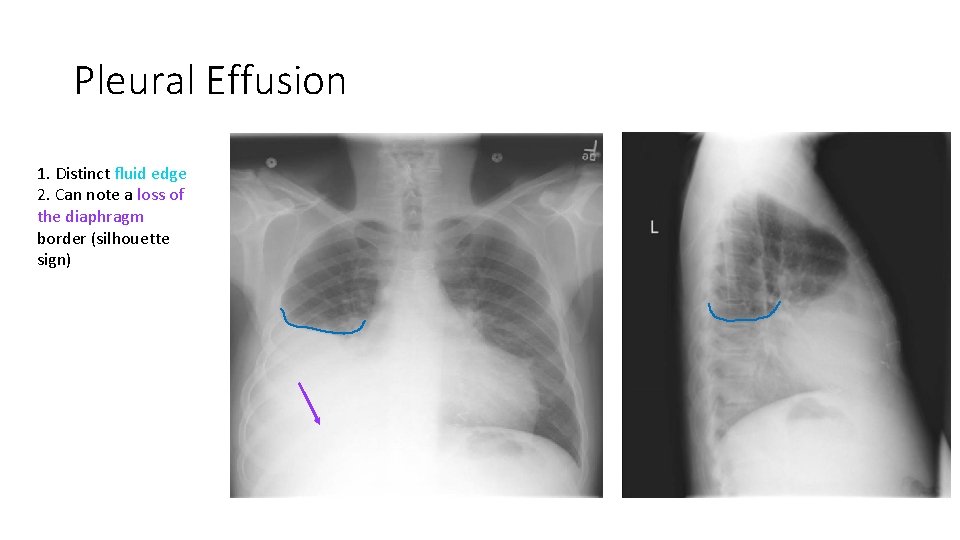

Pleural Effusion 1. Distinct fluid edge 2. Can note a loss of the diaphragm border (silhouette sign)